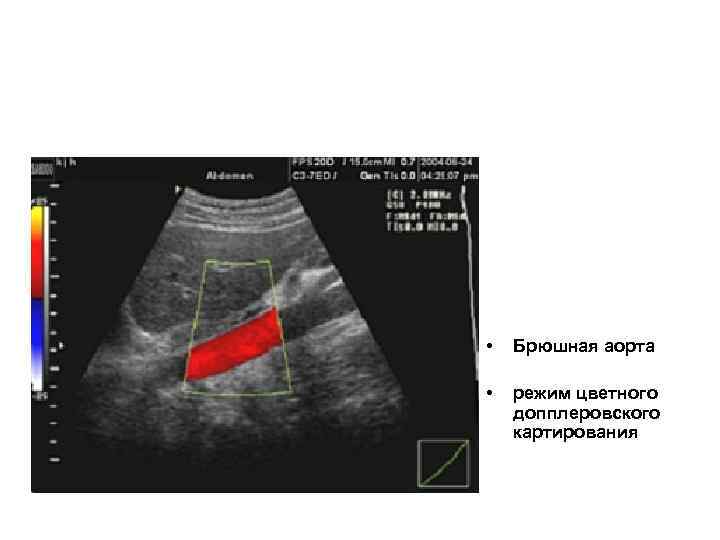

• Брюшная аорта • режим цветного допплеровского картирования

• Брюшная аорта • режим цветного допплеровского картирования